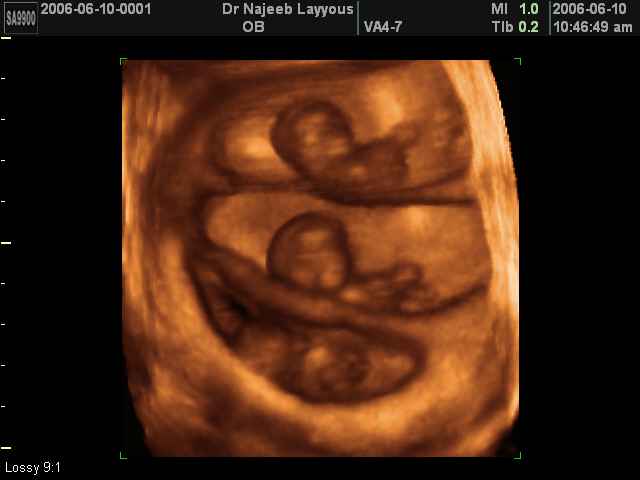

3D Photos échographie de grossesse multiple : Jumeaux, triplés et quadruples| Dr N Layyous

3D Photos échographie de grossesse multiple